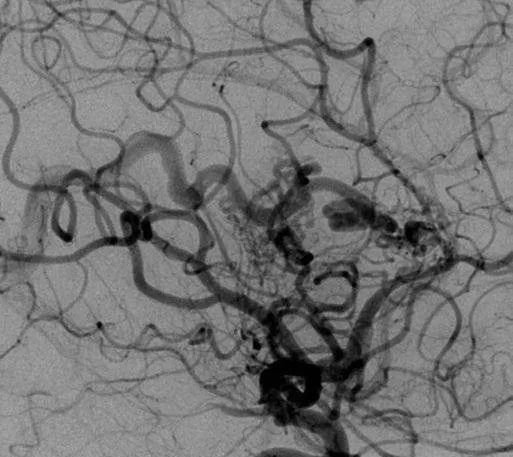

▼该AVM由ACA/PcaA分支、ACoA穿支和mPChA供血[右侧ICA造影

(a)侧位s(b)前斜位